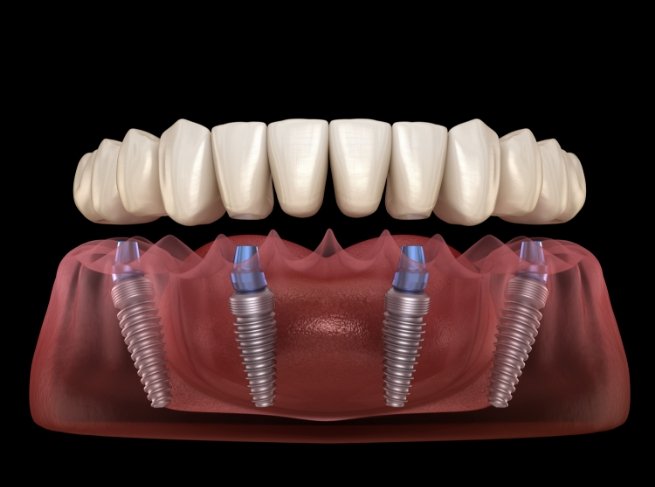

Dental implants are artificial tooth roots made of biocompatible titanium placed into the jawbone to replace missing teeth. They function like natural teeth and provide a strong foundation for crowns or bridges.

| All-on-4 (per arch) | ₹1,50,000 – ₹3,50,000 |

| All-on-6 (per arch) | ₹2,00,000 – ₹4,50,000 |